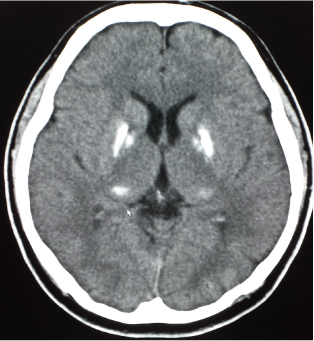

@EͺCTFΌ€ε]ξκjΞD»